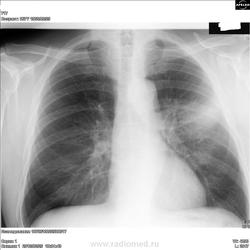

imcho:Я не вижу где затенение расположено в боковой проекции? Это точно R-грамма того же пациента? Конуры затенения нечёткие-это инфильтрат, вероятно пневмонического характера. Возможно температуры нет, потому что он перенёс её на ногах, а сейчас мы видим рентгенологический "хвост" пневмонии.

Лихорадки нет. Абсцедирующая в фазе инфильтрата отпадает. Интересна разница скиалогии по проекциям: в прямой - размытый инфильтрат с чем-то овальным в центре, в боковой - эдакий дендрит с усами. Ждем томки.

В аксиллярном субсегменте инфильтрация, более интенсивная в центре. Что то, кажется, "круглит". Выскажусь в пользу периферического

рака. Очень хочется ТГ. Надеюсь будут выставлены.Ждем продолжения.

В динамике уменьшение размеров затенения и появление очерченности контуров (?) Несколько непонятно...Такое впечатление, что имеет место пневмония с положительной динамикой в сочетании с чем-то.Для начала взял бы пациента за экран и в условиях полипозционного исследования попытался разобраться с субстратом патологии (или если есть возможность КТ лёгких) . Неполохо было бы поднять ФЛО архив, может быть что-то в этом месте было и раньше. Ну, а пока можно предложить следующий дифференциально-диагностический ряд:

1.Тромбоэмболия лёгочной артерии осложнённая пневмонией.

2.Периферический рак в сочетании с пневмонией с локализацией в S3.

3.Пневмония в сочетании с ограниченным пневмофиброзом.

4.Междолевой плеврит